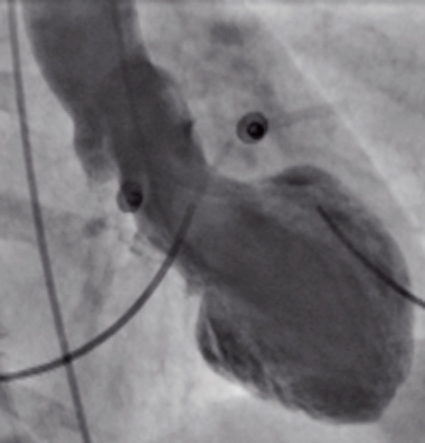

På grund av diskrepansen mellan patientens symtom och undersökningsfynden utfördes en ventrikulografi som uppenbarade ett, för oss, överraskande fynd (Figur 3). Den visade att de apikala delarna av hjärtat var akinetiska trots att de resterande basala delarna av hjärtat var hyperkinetiska.